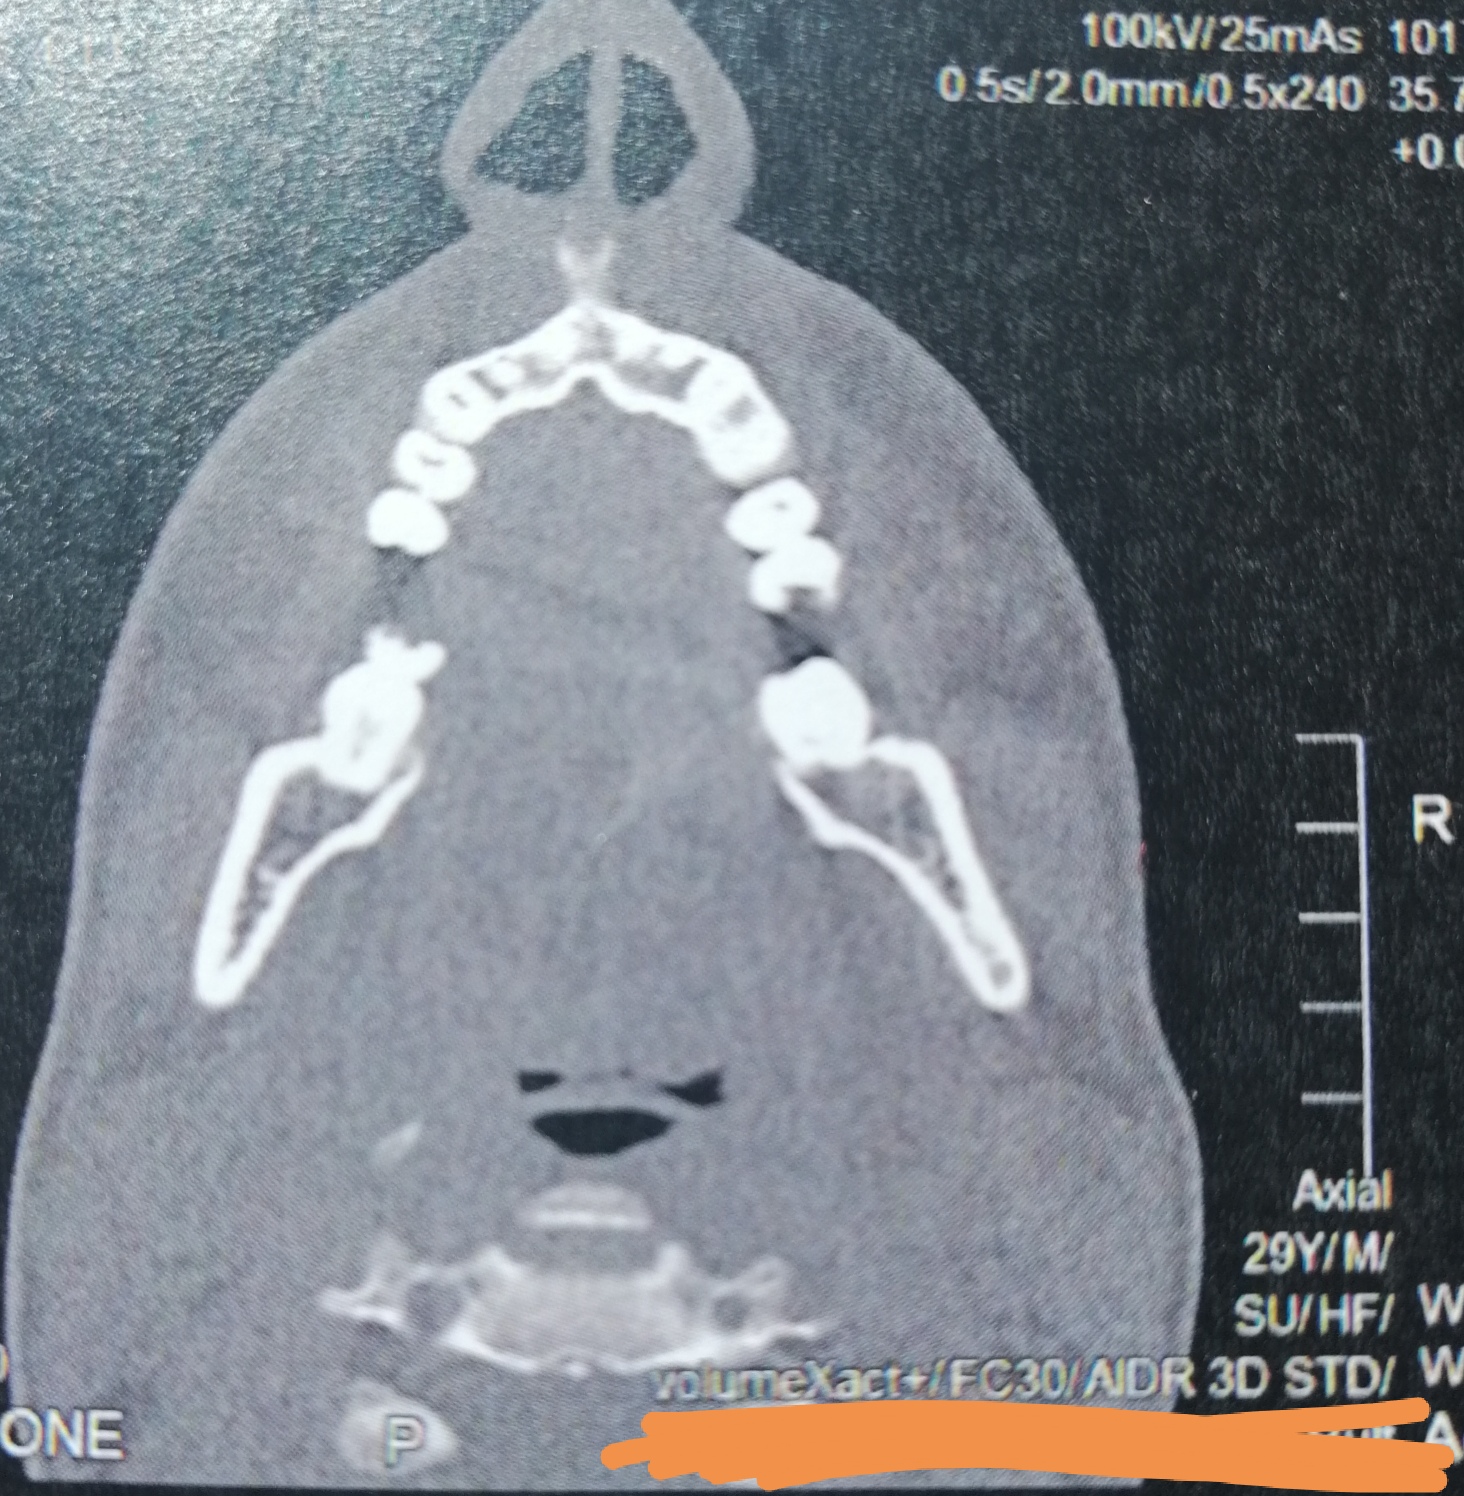

CT der Nasennebenhöhlen /Nase, alles ok? (kernspintomographie)